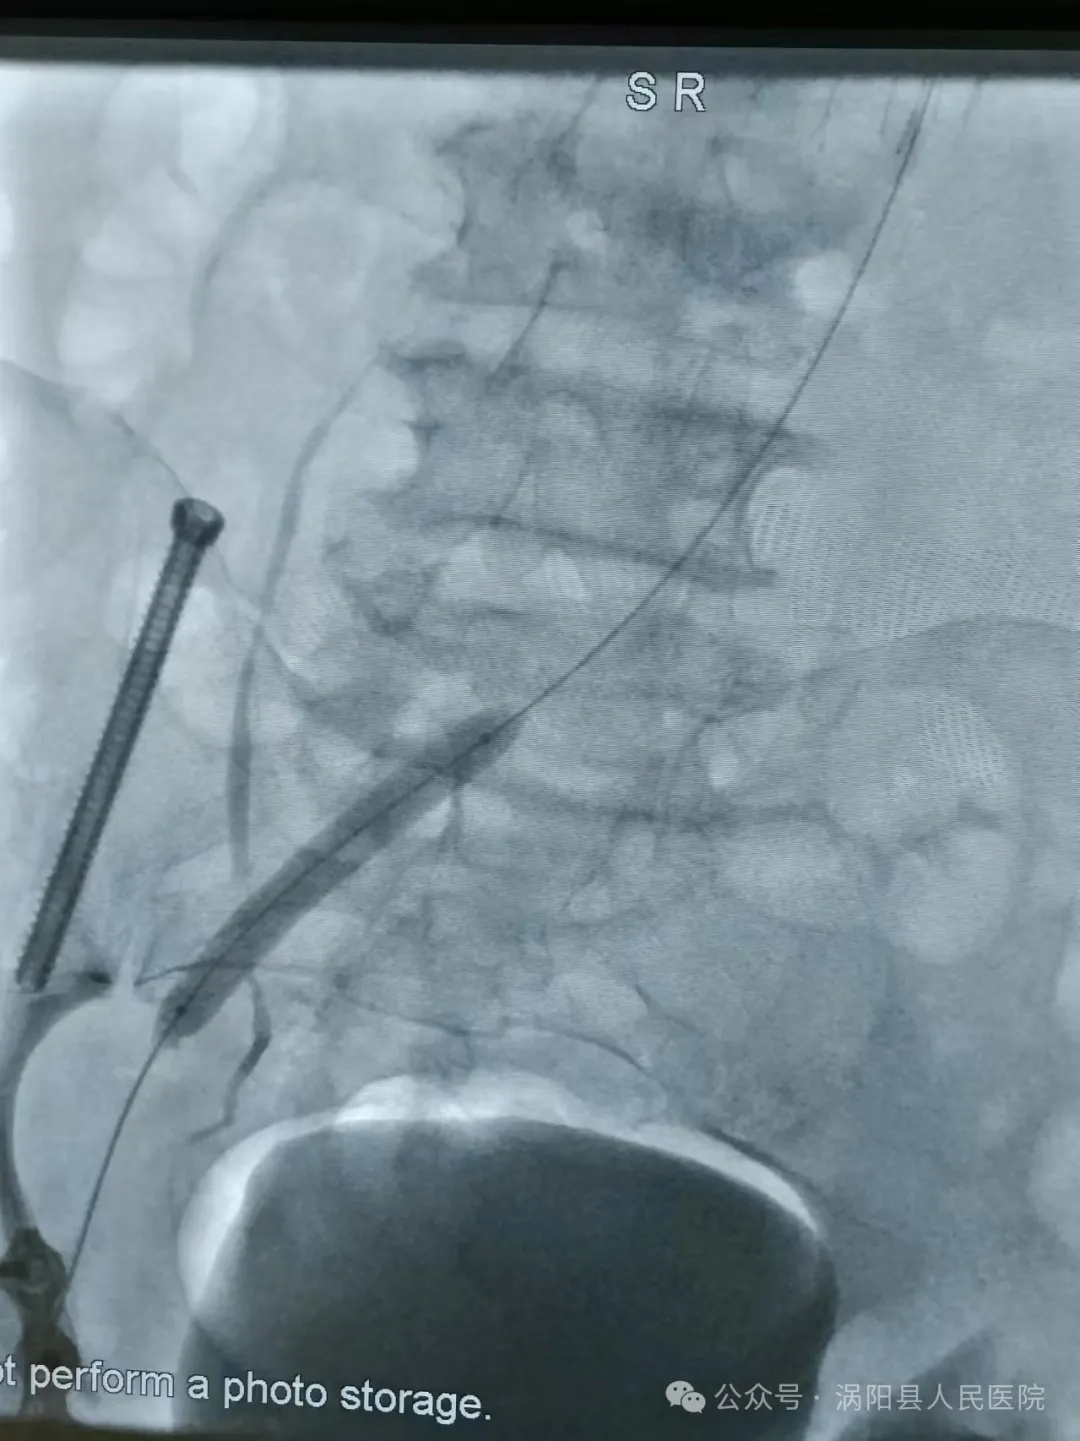

因左髂静脉被右髂动脉及第五腰椎棘突前后压迫,及左髂静脉汇入下腔静脉的角度较大(接近90°),下肢DVT(深静脉血栓形成)患者多发生于左下肢,且近80%以上合并有左髂静脉狭窄。所以在下肢DVT(深静脉血栓形成)治疗过程中解决左髂静脉狭窄问题十分必要,目前多以血管腔内成型为主的微创手术方式为主。

放置溶栓导管

导管直接接触溶栓(Catheter-Directed Thrombolysis, CDT),目前是各种指南推荐级别较高的一种DVT(深静脉血栓形成)的治疗手段,溶栓药物经过溶栓导管的侧孔直接进入血栓的内部,直接接触血凝块,溶栓效果良好。

置管溶栓 出院时